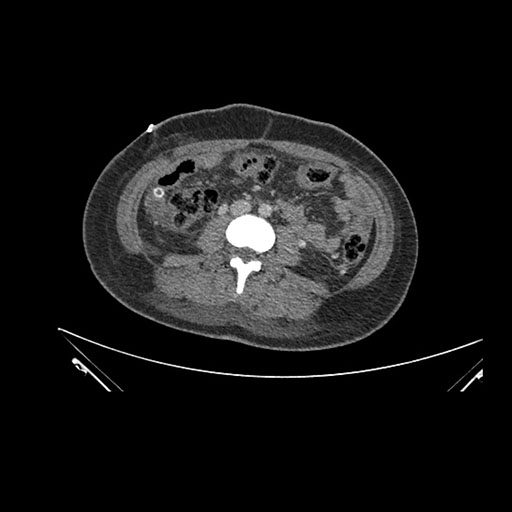

Axial Arterial

Imaging analysis

Based on initial findings, which issue(s) would you be most concerned about?